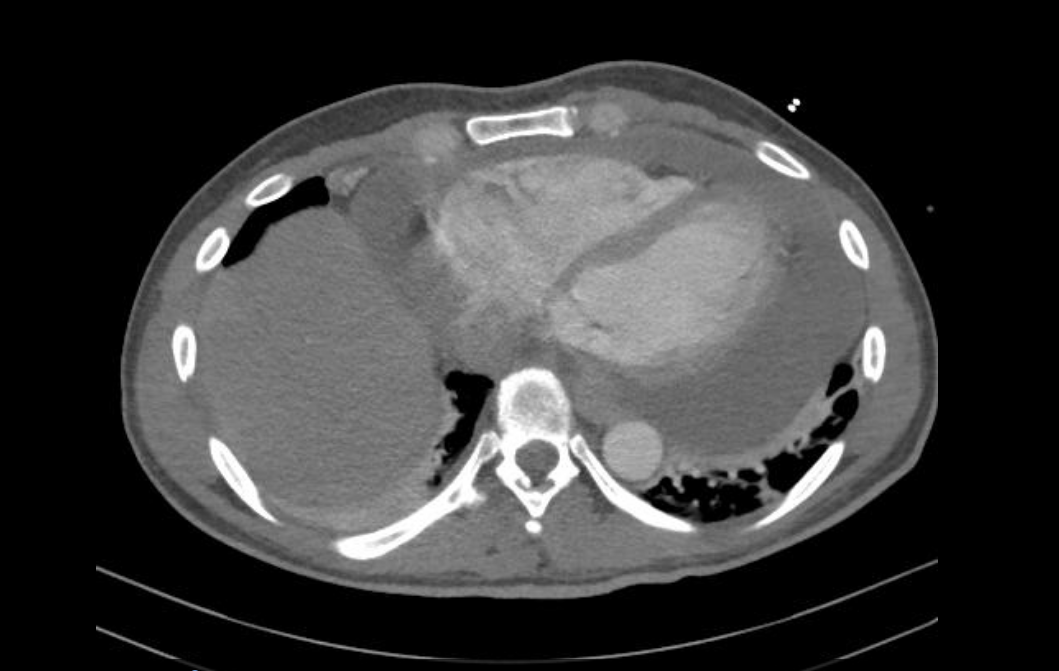

Computed tomography of the chest with verification of extensive pericardial effusion.

Case summary: A 47-year-old male presented with sudden chest pain and shortness of breath. Echocardiography revealed pericardial tamponade along with pleural effusion over time. Campylobacter jejuni was identified by microbiological analysis in pericardial aspirates and stool samples without prior gastrointestinal complains.